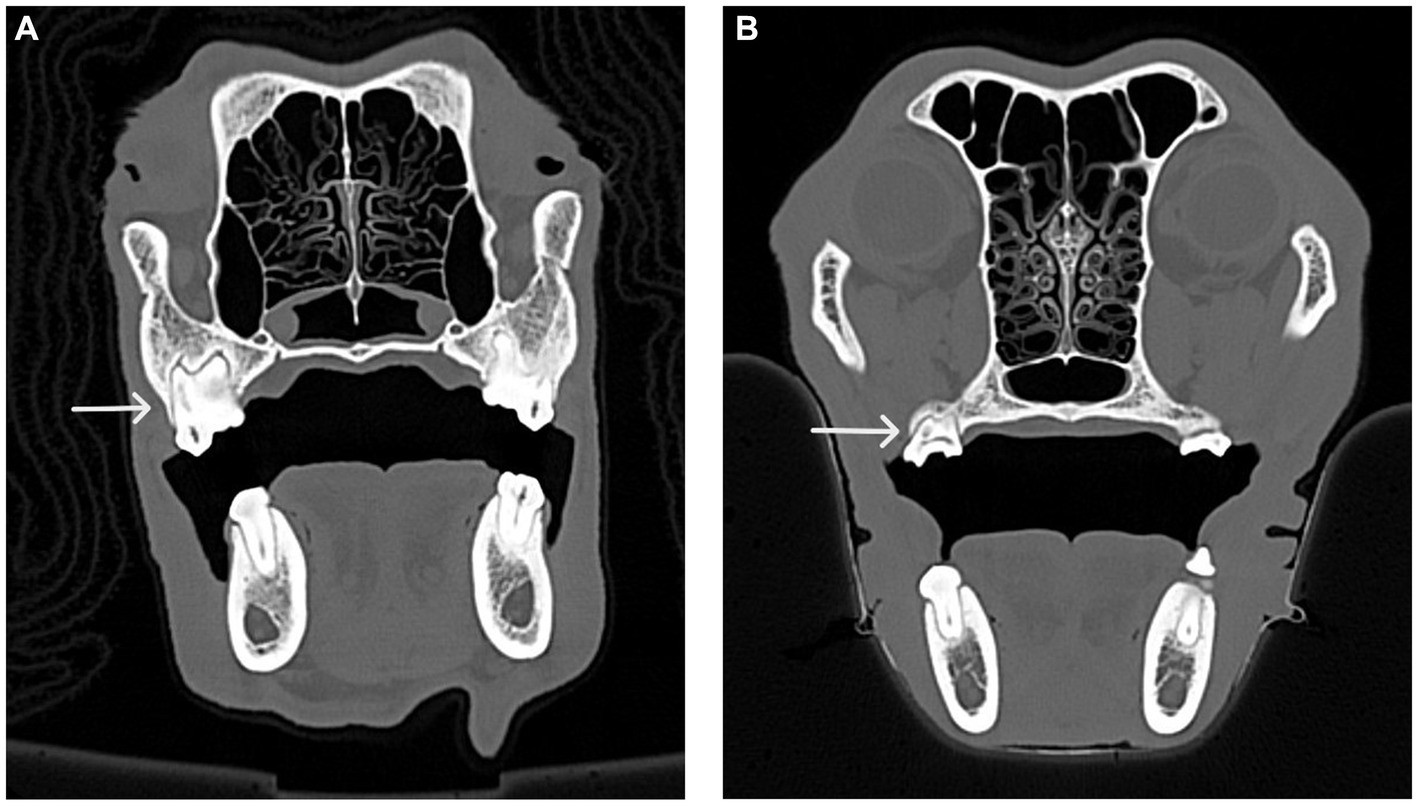

Figure 7

CT scans of a dog skull, labeled A and B. Image A shows a transverse view with an arrow pointing to the first maxillary molar tooth with fused roots on the right side. Image B depicts a similar angle with an arrow indicating a second maxillary molar tooth with fused roots on the right side. Both scans highlight sinus cavities and jaw details.

Figure 7. CT images of the transverse view of dog skulls showing the fusion of roots in the maxillary first molar tooth and the maxillary second molar tooth. (A) This CT image shows fusion (white arrow) of the distal buccal root with the palatal root of the maxillary first right molar tooth in a dog. (B) This CT image shows fusion (white arrow) of the distal buccal root with the palatal root of the right maxillary second molar tooth in a dog.